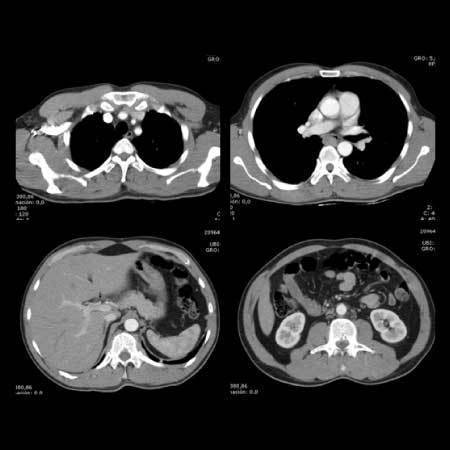

¿Qué tipo de estudio es?

Image:

T Torax C01 (image/jpeg)

Answer

Resonancia magnética

Radiografía

Ecografía

Tomografía